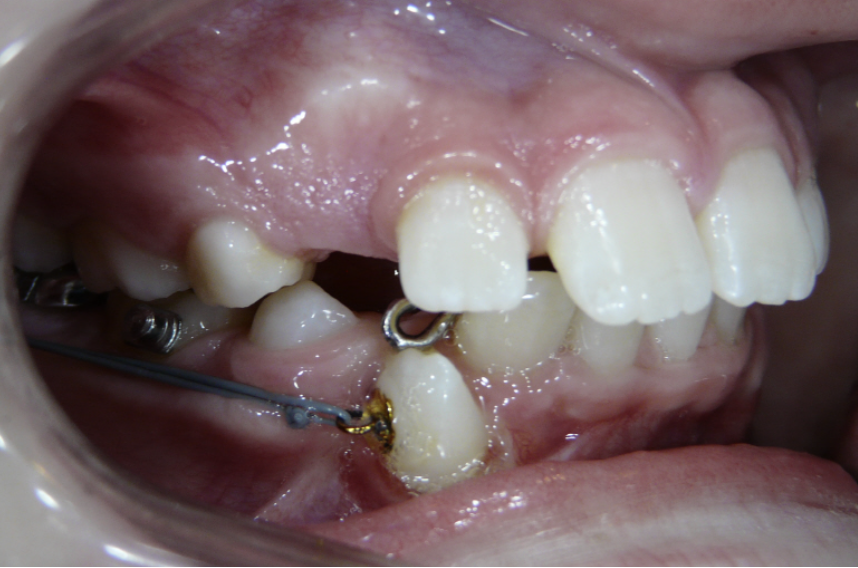

Ectopic Eruption

Ectopically erupting maxillary molar